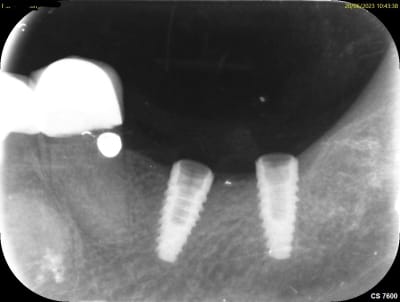

J'ai un implant mystère, posé il y a une quinzaine d'année à Djibouti, le praticien est décédé... Une idée?

Un train peut en cacher un autre, au sein de la même matinée, posé il y a 15 ans, Serf ou Zimmer selon le patient...

Le premier SERF EVLN

le second TSV Zimmer